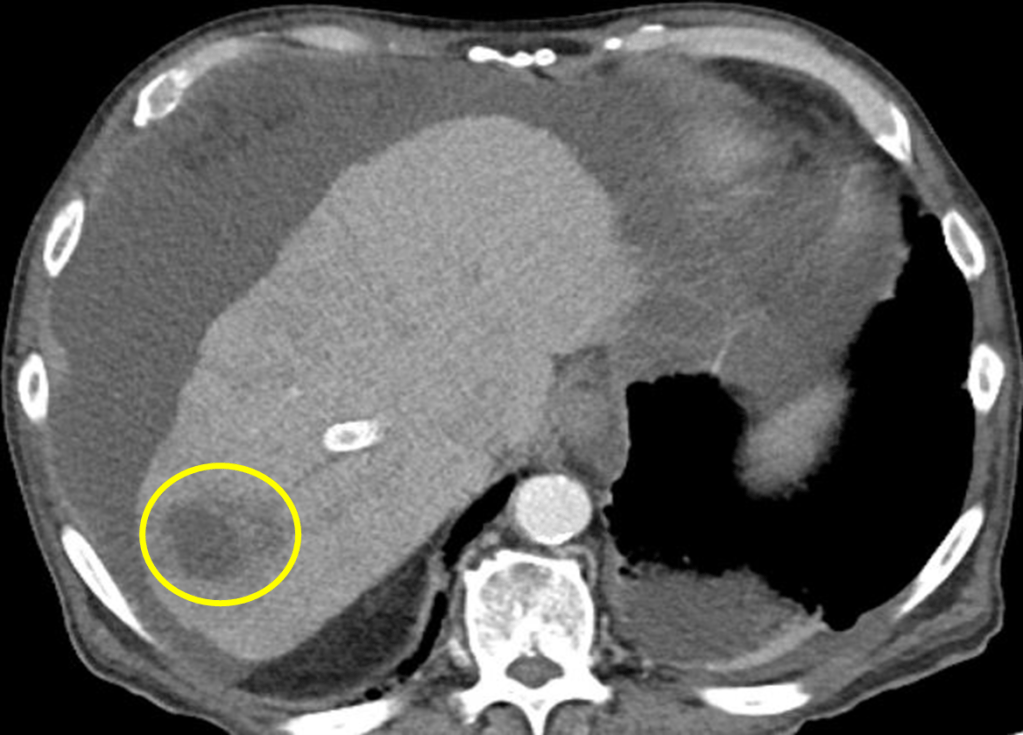

A middle age male with a past medical history of liver cirrhosis presented to the emergency department with one day of fever, chills, generalized weakness, and nausea. Complete blood count with differential showed leukopenia and neutropenia. Infectious work up was initiated including collection of 2 sets of blood cultures and imaging studies. A computed tomography (CT) scan of the abdomen revealed an irregularly shaped hypodense lesion in the right hepatic lobe concerning for abscess (Image 1). Ultrasound guided aspiration for the hepatic lesion yielded cloudy yellow bilious fluid, which was sent to the microbiology lab for aerobic and anaerobic cultures.